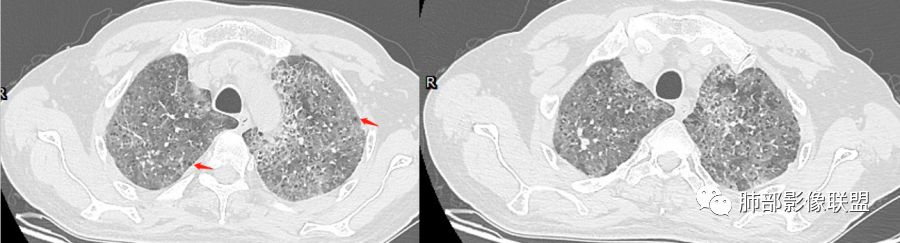

碎石路征,下肺为主

肺部结节

双侧小叶间隔增厚、对称

南边:只有GGO+网格(小叶间隔增厚),然后就是分布的问题

1、GGO+网格——碎石路征

4、小叶间隔内静脉增粗

5、病灶较多时部分可见重力趋势

2.由液体、细胞浸润和纤维组织造成的小叶间隔增厚是影像上多边形“铺路石征”的基础。

3.显眼的小叶间隔对病灶有阻挡作用是形成影像上“地图样改变”的基础。我们观察到的病灶与临近相对正常肺组织之间常常有比较清楚的分界。

这种表现颇具特征性。但有部分患者(1/4)仅有磨玻璃影而未显示小叶间隔增厚,这种情形我们很难将PAP列为第一诊断。